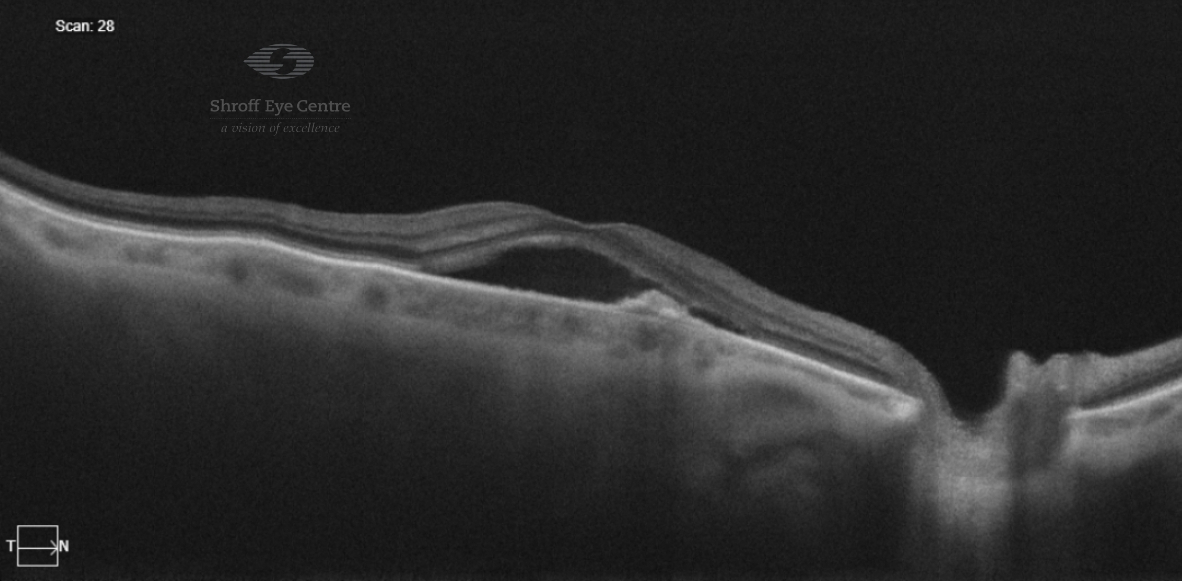

Optical Coherence Tomography (OCT)

- OCT provides cross-sectional images of retinal layers and detects any fluid accumulation, deposition of protein (drusen), and any structural changes in the macula and retina

- OCT is the gold standard for AMD diagnosis and monitoring the treatment

- OCT is essential for treatment planning and monitoring of AMD